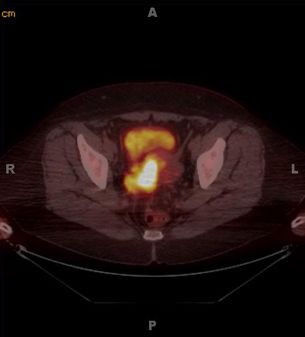

В первую очередь, это постановка правильного диагноза и назначение корректной терапии при выявлении злокачественных опухолей. Особенно эффективна МРТ при раке шейки матки, а МРТ-диагностика рака простаты выявляет более 50% случаев данного заболевания. Хорошо виден рак яичников на МРТ-снимках, в том числе степень его распространения в соседние органы и ткани. Это же относится к раку предстательной железы. Исследование позволяет точно определить локализацию новообразования, его точные размеры, наличие метастазов, степень поражения органа. К примеру, своевременная МРТ рака мочевого пузыря в подавляющем большинстве случаев дает возможность сохранить орган и не допустить распространения метастазов в почки, позвоночник, органы репродукции.

Стоит отметить, что МРТ нередко используют для выявления распространения раковых опухолей в организме. Таким образом, можно, выявить и принять своевременные меры по излечению от такого опасного заболевания.

МРТ малого таза с контрастом позволяет выявить заболевания, когда ни один другой метод диагностики не способен поставить точный диагноз. Использование контрастного усиления даёт возможность точно диагностировать заболевание, выявить опухоль, установить стадию процесса и назначить своевременное лечение.